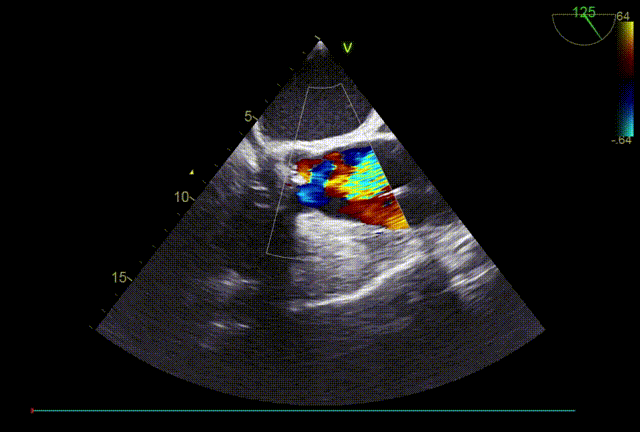

左冠风险评估

瓣膜内22mm球囊后扩张,左冠无显影

LM烟囱支架植入4.0*30mm

TTE